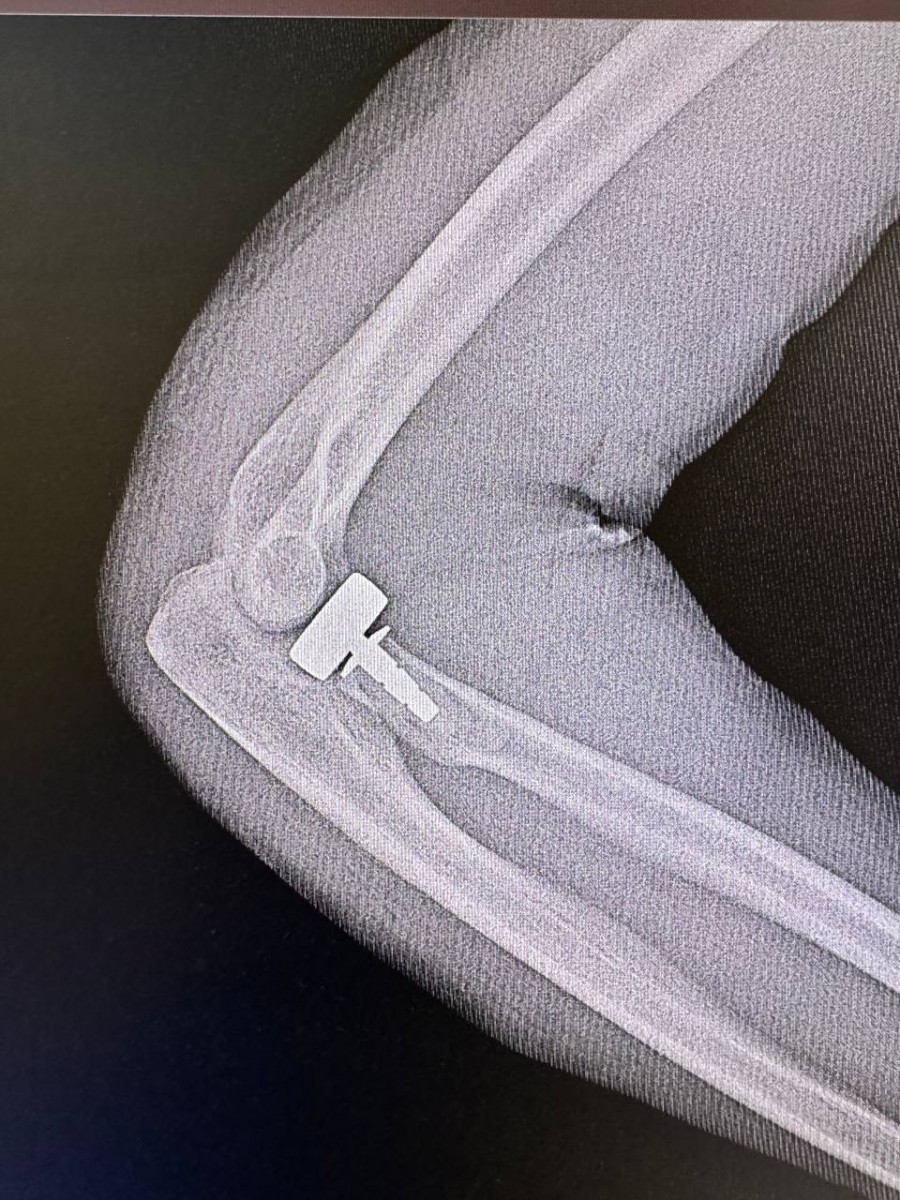

02.08.2024Сотрудники Центра хирургии и травматологии выполнили биполярное эндопротезирование головки лучевой кости после оскольчатого перелома. Такой метод позволит локтевому суставу 23-летнего пациента функционировать более естественно.